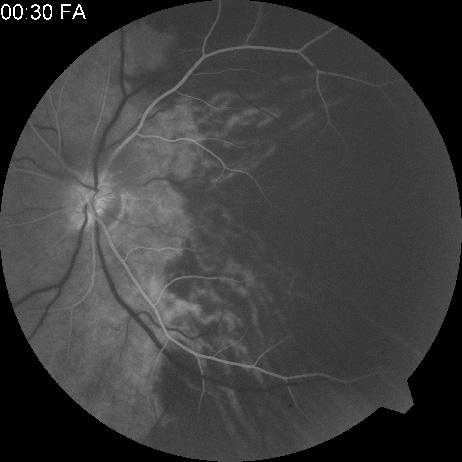

Cilioretinal arteries can be selectively obstructed (Fig. 3). More commonly, however, they occur in association with central retinal vein obstruction.113 When they supply a significant portion of the macula, decreased visual acuity is common. Prognosis for visual outcome in such patients is good. Brown and co-workers114 studied 10 eyes having an isolated cilioretinal artery obstruction. Of those, 60% had an initial visual acuity of 20/40 or better and on follow-up examination, all eyes but one had a best-corrected visual acuity of 20/40 or better.114

Fig. 3. A: Cilioretinal artery obstruction showing opacity of the retina in the area of obstruction. B: The cilioretinal artery has begun to fill after the branches of the central retinal artery but is still not completely filled at this point in the angiogram.